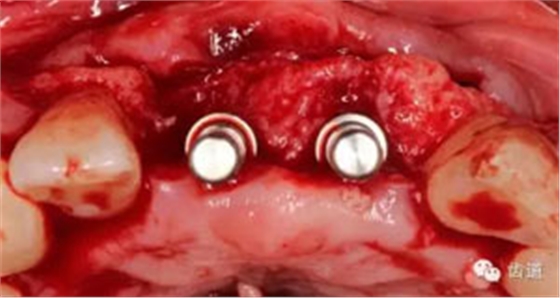

患者對(duì)美觀要求較高,與患者溝通后,擬定采用骨環(huán)技術(shù),同期種植并增加骨寬度和高度。

患者不愿才用自體骨移植,遂建議采用同種異體骨骨塊(皮質(zhì)骨)進(jìn)行骨環(huán)手術(shù)。 種植手術(shù):